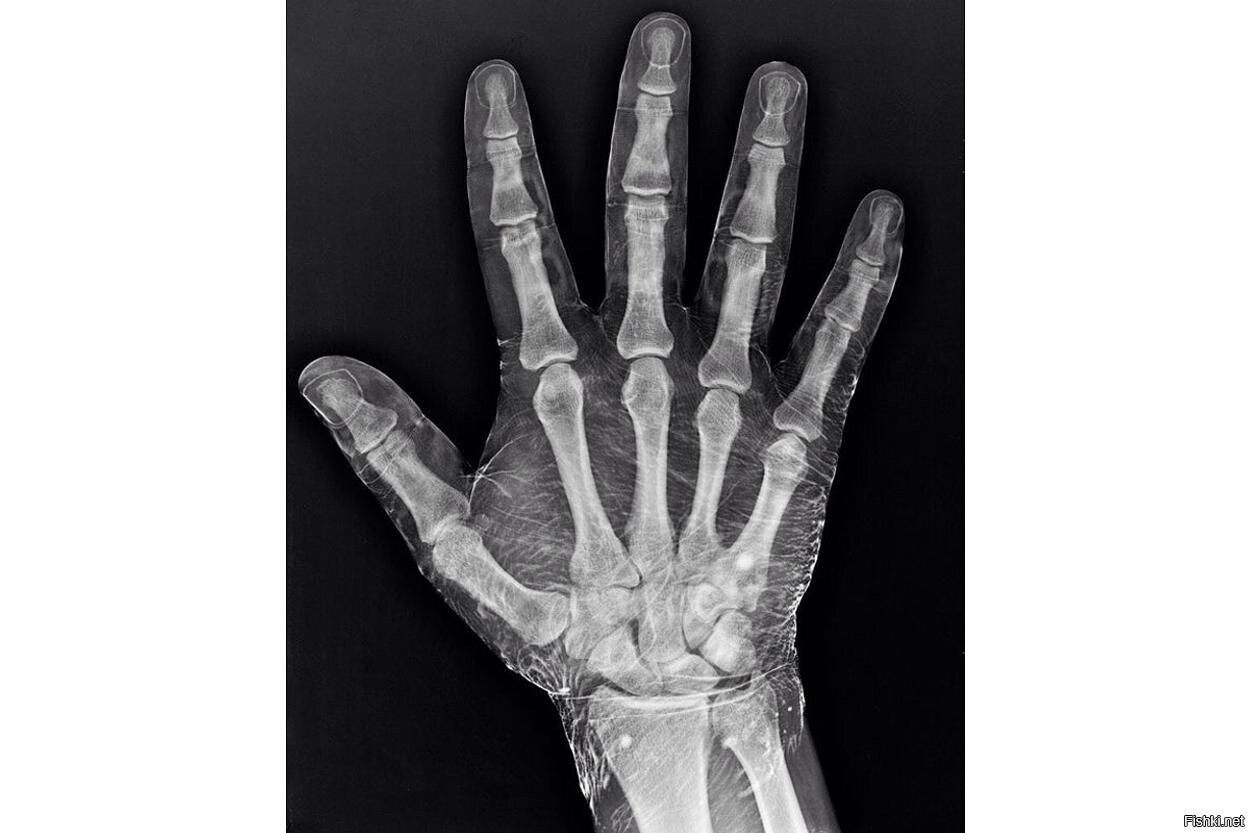

Рентген руки, смоченной в йоде

Йод поглощает рентгеновские лучи, что позволяет видеть кожу вокруг костей